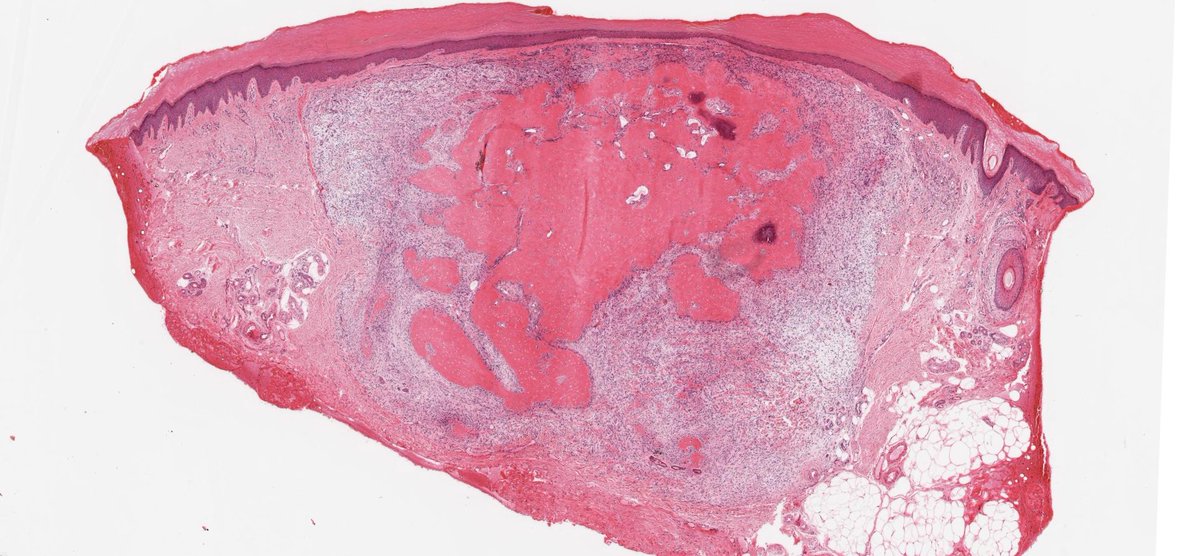

Two ossifying cutaneous tumours on PathPresenter as "ossifying fibromyxoid tumour". But they are quite different (pattern of ossification and arrangement of cells). The second is an example of ossifying plexiform tumour journals.lww.com/amjdermatopath… #pathology #dermatopathology

Two  ossifying cutaneous tumours on PathPresenter as "ossifying fibromyxoid tumour".  But they are quite different (pattern of ossification and arrangement of cells). The second is an example of ossifying plexiform tumour  journals.lww.com/amjdermatopath…

#pathology #dermatopathology